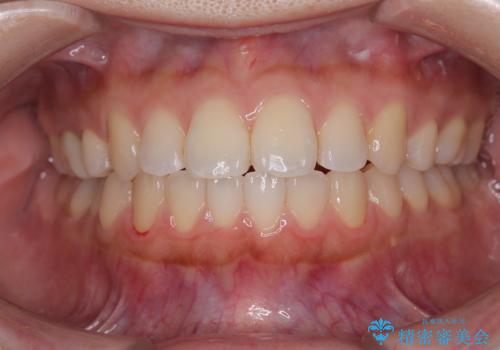

【審美装置】前歯で噛めない!抜歯しないで治したい

MARPEで非抜歯矯正|オープンバイトと八重歯を改善